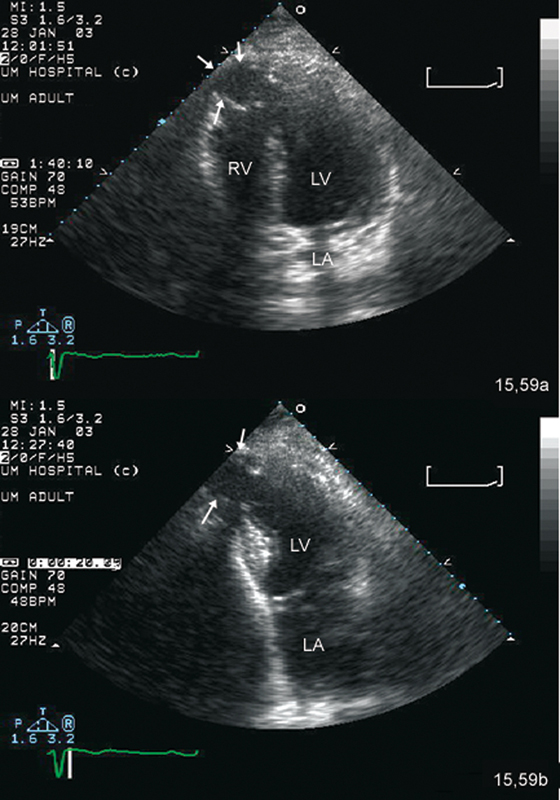

فحوصات تشخيصية لبعض امراض القلب والشرايين التاجية